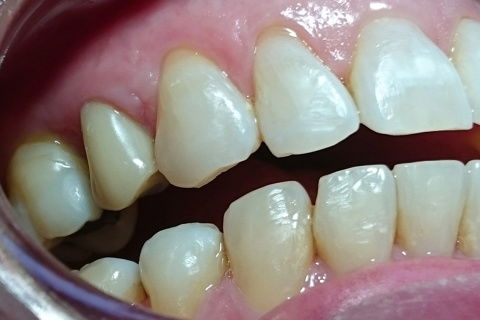

Vista lateral 15 dias após reabertura e função tardia.

Paciente sexo feminino,aproximadamente 40 anos, encaminhada pelo protesista para exodontia do elemento 14 e implantação. O mesmo verificou trinca na raíz do elemento 14. Após documentação e paciente avaliado o tratamento de opção em comum acordo com a paciente foi , exodontia, implante imediato com ROG (alobone) e enxerto gengival livre para ocluir o alvéolo, com provisório tipo aleta e função tardia. (Caso em andamento).